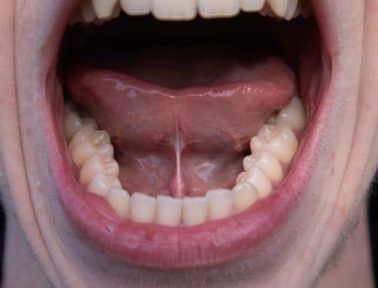

Dec 05

Ankyloglossia, commonly known as tongue tie, is a condition that affects nearly 5% of newborns. Tongue tie occurs when the thin piece of skin beneath the tongue, called the lingual frenulum, restricts the tongue’s range of motion. This condition